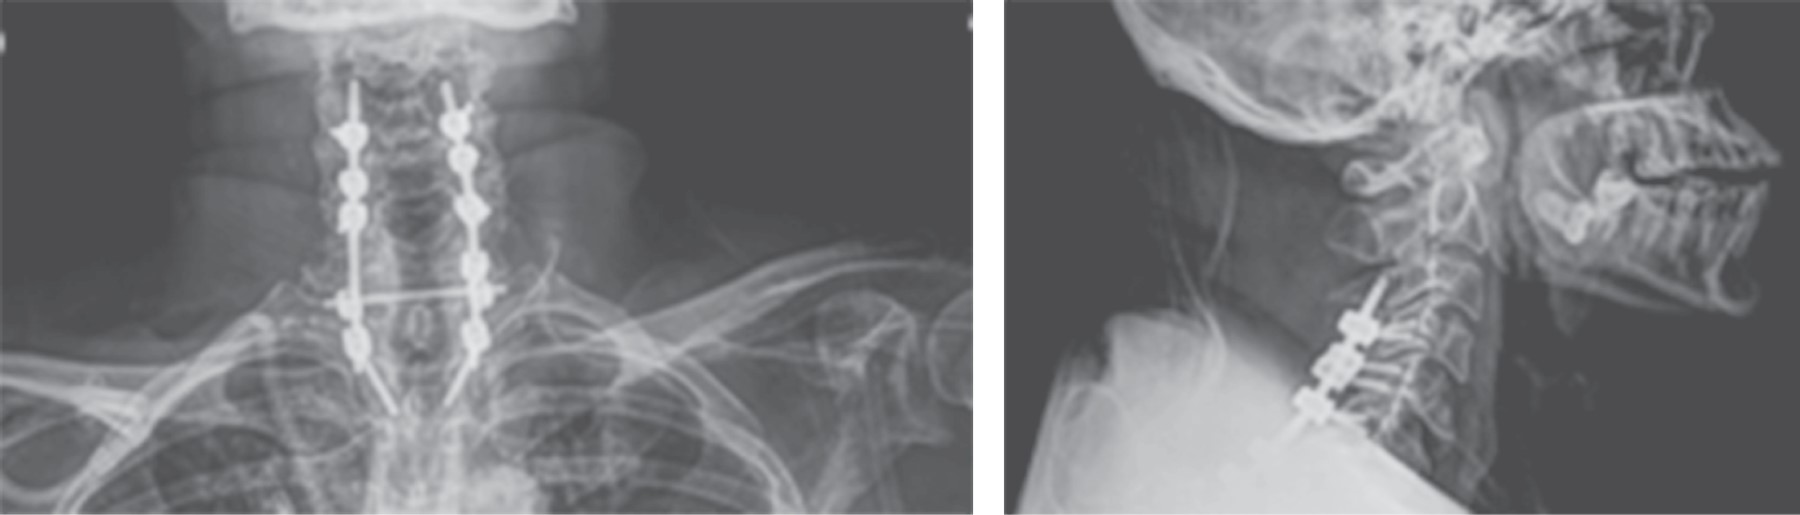

Figure 2

Figure 3